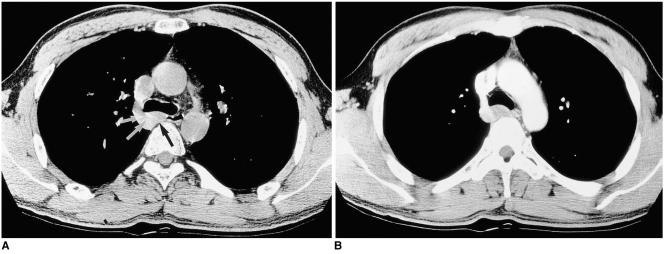

The tumors, surgical specimens of which ranged from 9 to 90 mm in diameter, were located in the upper (n = 1), middle (n = 5), or lower esophagus (n = 6). In ten of the 12 patients, chest radiography revealed the tumors as mediastinal masses. Esophagography showed them as eccentric, smoothly elevated filling defects in 11 patients and a multilobulated encircling filling defect in one. In 11 of the 12 patients, enhanced CT scans revealed a smooth (n = 9) or lobulated (n = 2) tumor margin, and attenuation was homogeneously low (n = 7) or iso (n = 4). In one patient, the tumor signal seen on T2-weighted MR images was slightly high.

Esophageal leiomyomas, located mainly in the middle or distal esophagus, are consistently shown by esophagography to be mainly eccentrically elevated filling defects and at CT, lesions showing homogeneous low or isoattenuation are demonstrated.